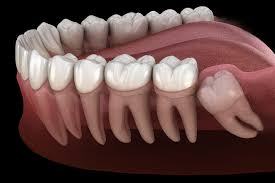

사랑니는 치아 중 가장 나중에 나고 자라므로 턱뼈에 공간이 부족하면 똑바로 나오지 못하고 주변의 잇몸을 괴롭히면서 통증을 유발한다고 한다.

완전히 나오지 않은 사랑니를 빼는 건 복잡한 수술 중 하나라고 한다.

하악골(아래턱뼈) 속에는 입술과 잇몸의 감각을 느끼게 하는 신경이 지난다고 한다.

상악골(위턱뼈) 속에는 축농증이 일어날 수 있는 부분인 상악동이 있다고 한다.

이들이 사랑니 뿌리와 근접하거나 겹쳐 있는 경우가 종종 있다고 한다.